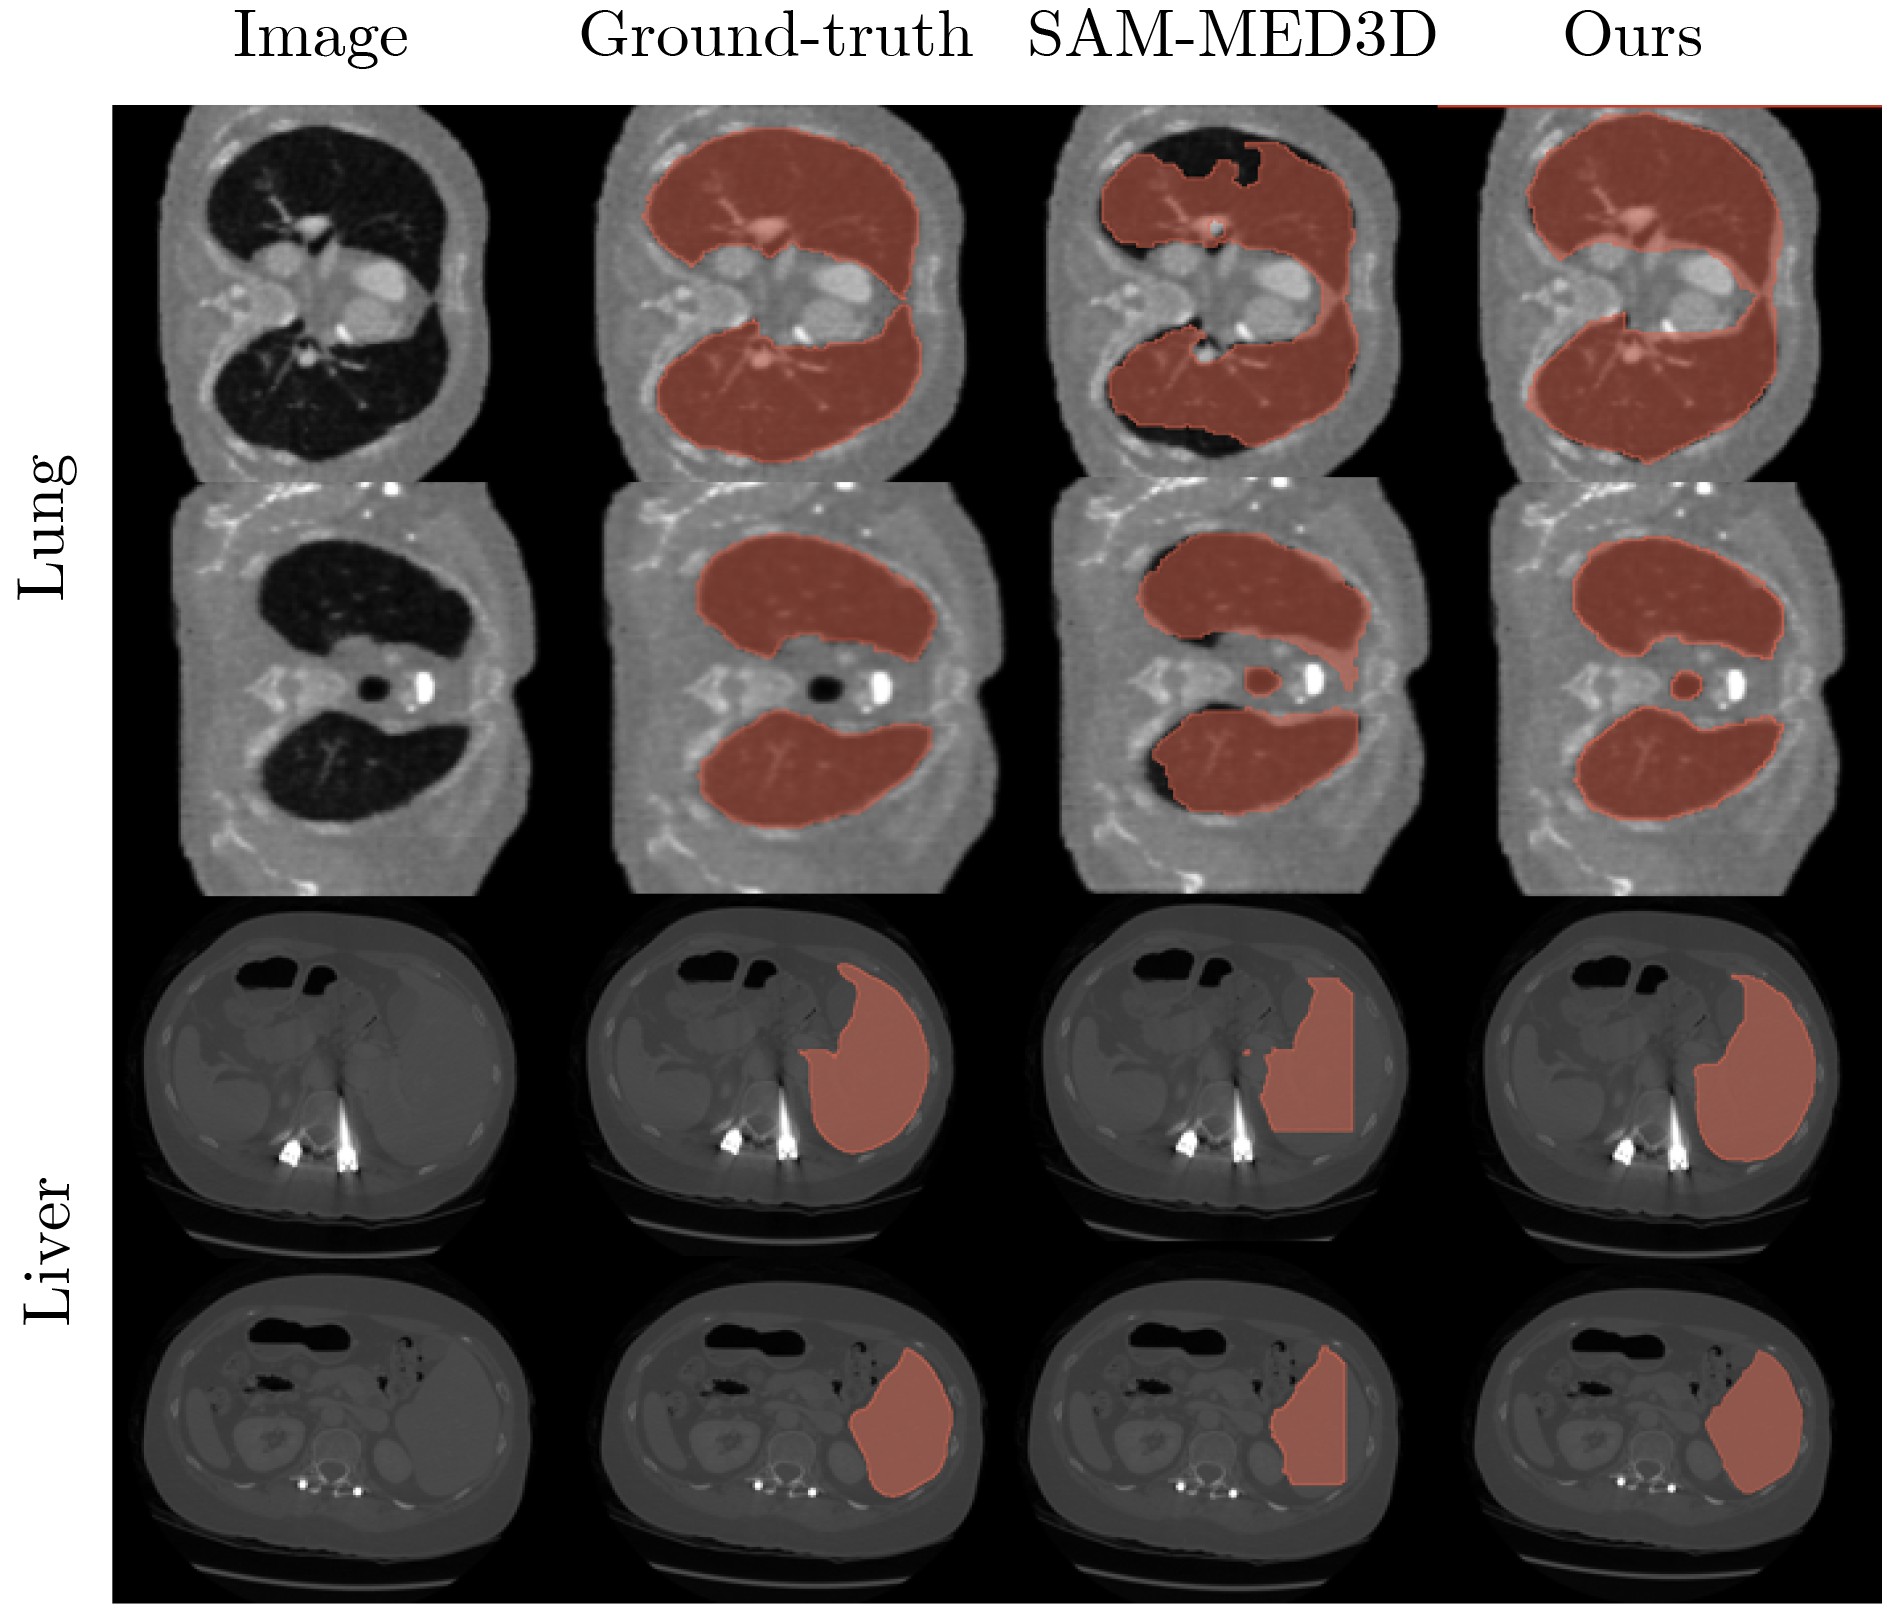

Objective Three-dimensional medical image segmentation is a central task in medical image analysis. Compared with two-dimensional imaging, it captures organ and lesion morphology more completely and provides detailed structural information, supporting early disease screening, personalized surgical planning, and treatment assessment. With advances in artificial intelligence, three-dimensional segmentation is viewed as a key technique for diagnostic support, precision therapy, and intraoperative navigation. However, methods such as SwinUNETR-v2 and UNETR++ depend on extensive voxel-level annotations, which create high annotation costs and restrict clinical use. High-quality segmentation also often requires multi-view projections to recover full volumetric information, increasing radiation exposure and patient burden. Segmentation under sparse radiation measurements is therefore an important challenge. Neural Attenuation Fields (NAF) have recently been introduced for low-dose reconstruction by recovering linear attenuation coefficient fields from sparse views, yet their suitability for three-dimensional segmentation remains insufficiently examined. To address this limitation, a unified framework termed NA-SAM3D is proposed, integrating NAF-based reconstruction with interactive segmentation to enable unsupervised three-dimensional segmentation under sparse-view conditions, reduce annotation dependence, and improve boundary perception. Methods The framework is designed in two stages. In the first stage, sparse-view reconstruction is performed with NAF to generate a continuous three-dimensional attenuation coefficient tensor from sparse X-ray projections. Ray sampling and positional encoding are applied to arbitrary three-dimensional points, and the encoded features are forwarded to a Multi-Layer Perceptron (MLP) to predict linear attenuation coefficients that serve as input for segmentation. In the second stage, interactive segmentation is performed. A three-dimensional image encoder extracts high-dimensional features from the attenuation coefficient tensor, and clinician-provided point prompts specify regions of interest. These prompts are embedded into semantic features by an interactive user module and fused with image features to guide the mask decoder in producing initial masks. Because point prompts provide only local positional cues, boundary ambiguity and mask expansion may occur. To address these issues, a Density-Guided Module (DGM) is introduced at the decoder output stage. NAF-derived attenuation coefficients are transformed into a density-aware attention map, which is fused with the initial masks to strengthen tissue-boundary perception and improve segmentation accuracy in complex anatomical regions. Results and Discussions NA-SAM3D is evaluated on a self-constructed colorectal cancer dataset comprising 299 patient cases (collected in collaboration with Nanjing Hospital of Traditional Chinese Medicine) and on two public benchmarks: the Lung CT Segmentation Challenge (LCTSC) and the Liver Tumor Segmentation Challenge (LiTS). The results show that NA-SAM3D achieves overall better performance than mainstream unsupervised three-dimensional segmentation methods based on full radiation observation (SAM-MED series) and reaches accuracy comparable to, or in some cases higher than, the fully supervised SwinUNETR-v2. Compared with SAM-MED3D, NA-SAM3D increases the Dice on the LCTSC dataset by more than 3%, while HD95 and ASD decrease by 5.29 mm and 1.32 mm, respectively, indicating improved boundary localization and surface consistency. Compared with the sparse-field-based method SA3D, NA-SAM3D achieves higher Dice scores on all three datasets ( Table 1 ). Compared with the fully supervised SwinUNETR-v2, NA-SAM3D reduces HD95 by 1.28 mm, and the average Dice is only 0.3% lower. Compared with SA3D, NA-SAM3D increases the average Dice by about 6.6% and reduces HD95 by about 11 mm, further confirming its capacity to restore structural details and boundary information under sparse-view conditions (Table 2 ). Although the overall performance remains slightly lower than that of the fully supervised UNETR++ model, NA-SAM3D still shows strong competitiveness and good generalization under label-free inference. Qualitative analysis shows that in complex pelvic and intestinal regions, NA-SAM3D produces clearer boundaries and higher contour consistency (Fig. 3 ). On public datasets, segmentation of the lung and liver also shows superior boundary localization and contour integrity (Fig. 4 ). Three-dimensional visualization further confirms that in colorectal, lung, and liver regions, NA-SAM3D achieves stronger structural continuity and boundary preservation than SAM-MED2D and SAM-MED3D (Fig. 5 ). The DGM further enhances boundary sensitivity, increasing Dice and mIoU by 1.20% and 3.31% on the self-constructed dataset, and by 4.49 and 2.39 percentage points on the LiTS dataset (Fig. 6 ).Conclusions An unsupervised three-dimensional medical image segmentation framework, NA-SAM3D, is presented, integrating NAF-based reconstruction with interactive segmentation to achieve high-precision segmentation under sparse radiation measurements. The DGM effectively uses attenuation coefficient priors to enhance boundary recognition in complex lesion regions. Experimental results show that the framework approaches the performance of fully supervised methods under unsupervised inference and yields an average Dice improvement of 2.0%, indicating strong practical value and clinical potential for low-dose imaging and complex anatomical segmentation. Future work will refine the model for additional anatomical regions and assess its practical use in preoperative planning. -